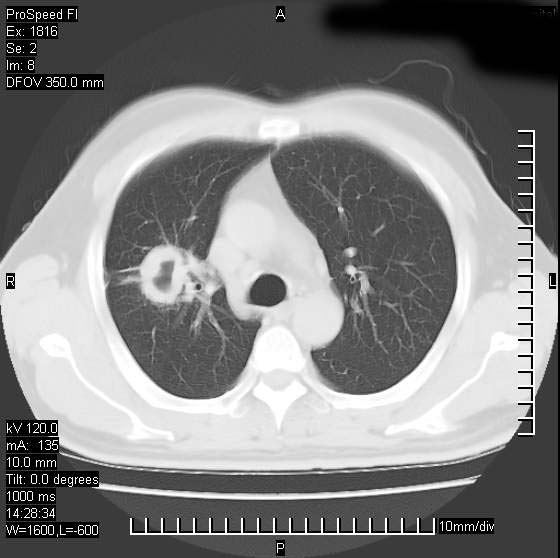

男性,50 ,肺结核9年,咳嗽,胸痛一周。右上肺见一厚壁空洞,周边有点样钙化,胸膜牵拉,洞壁较光整。诊断结核性空洞。有癌性的可能吗? 余肺野无异常,没有上传。

不像是肺ca倒更像一个结核空洞,因为看一下他内前方的支气管一点没有浸润征象只是压迫.

部分层面见空洞为近似新月形,洞壁内缘尚规整且近肺门侧,周围见索条影、卫星灶,结合病史,首先考虑肺tb可能大。

9年的结核应该呈现多形态病灶,该病例只能见到少许纤维索条影,似乎与结核的演变不太相符。空洞内壁不光整,外侧伴有胸膜粘连,考虑癌性空洞可能性大,期待结果。